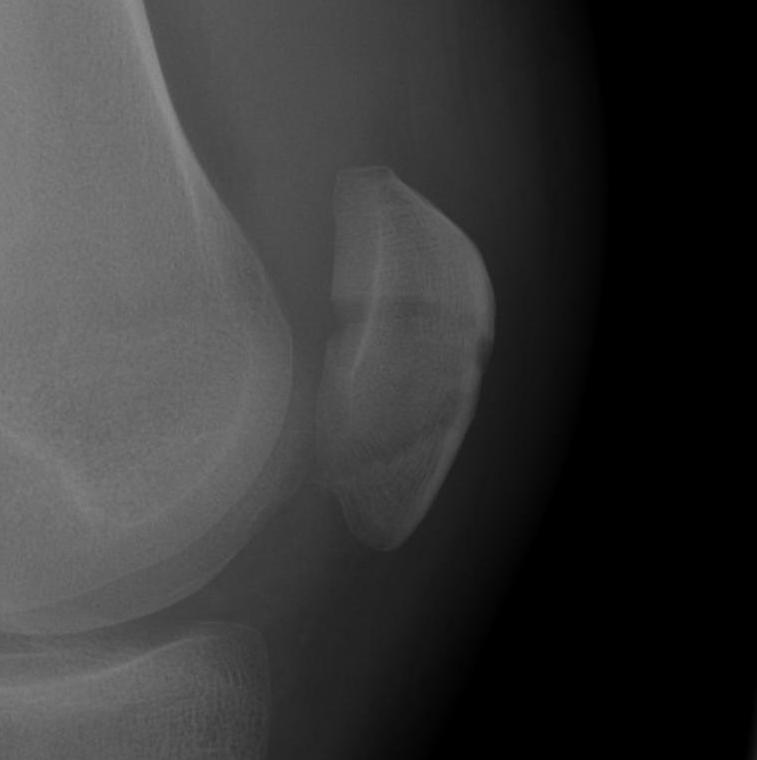

2. Transverse

Displaced transverse fractures